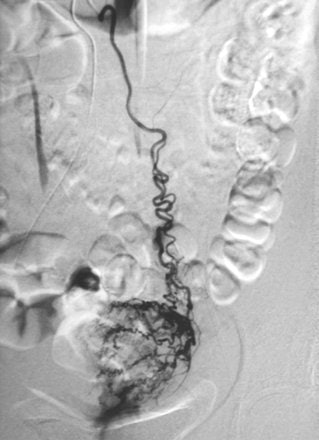

| A 42-year-old woman undergoing UAE for treatment of symptomatic uterine leiomyoma. Aortogram obtained after subsequent selection and contrast injection of left ovarian artery shows substantial supply to uterine fibroids that may cause UAE treatment to fail unless left ovarian artery is also embolized. Abbara S, Boris Nikolic B, Pelage JP, Banovac F, Spies JB, "Frequency and Extent of Uterine Perfusion via Ovarian Arteries Observed During Uterine Artery Embolization for Leiomyomas" (AJR 2007; 188:1558-1563). |

A total of 290 ovarian arteries were evaluated. Ovarian artery catheterization and injection were required in 61% of the visualized ovarian arteries. Of these, 69% showed residual fibroid perfusion. Perfusion scores for individual ovarian arteries ranged from one to 18 segments, the group reported.

The authors determined that the following criteria were significantly associated with the presence of fibroid supply, as well as the number of segments supplied by the ovarian arteries: larger ovarian arteries, visualization of flow, and flow extension into the pelvis.

The identification of these characteristics on flush aortogram indicated that OAE should be performed, Abbara and colleagues concluded. They explained that their current approach is to assess the extent of ovarian artery supply to fibroid tissue and, if there is evidence of extensive residual flow, to at least perform unilateral OAE.